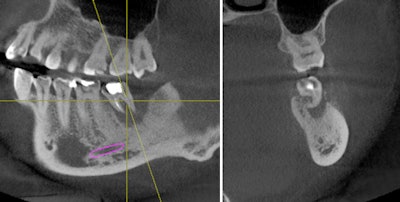

A 29-year-old woman presented for examination and consultation to diagnose a mildly symptomatic lower left second molar. Her previous dentist recommended she visit an endodontist for retreatment of this tooth.

Oral exam revealed a lower left second molar tooth with class III mobility and severe occlusal wear. Periapical pathology was present because of a poorly treated root canal. A CBCT scan gave us a clear understanding that tooth #18 was hopeless and was literally floating in pathology.

Incidental findings were present: a mesiodens in the area of #9 with an associated asymptomatic periapical lesion.